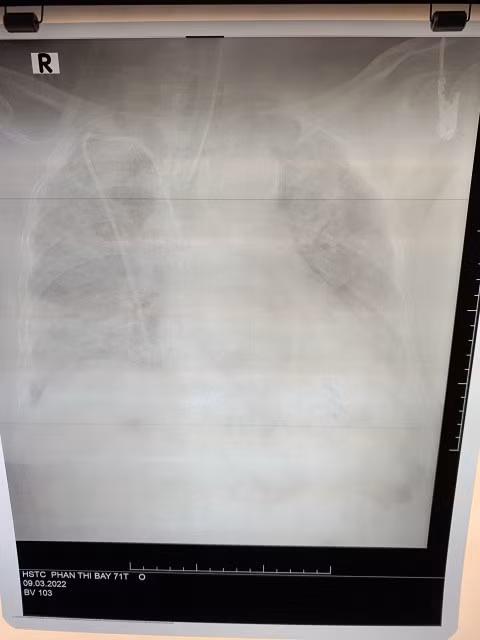

Khám thở nhanh nông tần số 35 chu kỳ/phút, đáp ứng kém với thở oxy mask 10 lít/phút, SpO2 chỉ đạt 70-80%, mạch 110 lần/phút, huyết áp 120/75mmHg, ý thức u ám, chỉ số BMI 31,5. X-quang phổi tổn thương kính mờ và đông đặc lan toả 2 phổi; test nhanh dương tính SARS-CoV-2.

Hình ảnh X-quang phổi tổn thương của bệnh nhân lúc vào viện. Ảnh: BV.